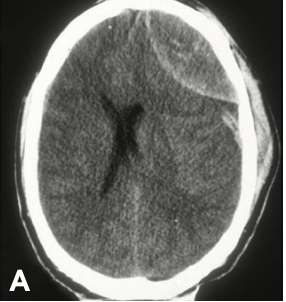

17

Q

Hematoma epidural

A

Forma de balón de americano

Lesión no puede atravesar subduras, por eso toman esa forma.

Origen arterial

Evolución más rápida, deterioro veloz

Desgarro arteria meníngea media en fractura (más común)

Lucidez a deterioro